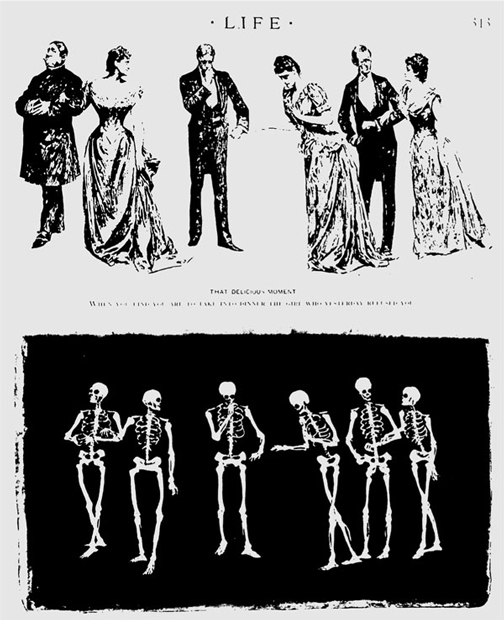

Selbst die renommierte Zeitschrift Life zeigte ihren Lesern die »aussichtsreichen« Einblicke mit Hilfe der X-Strahlen. Eine Abendgesellschaft, fotografiert einmal mit einem normalen Plattenapparat, unten mit Hilfe der Röntgenstrahlen